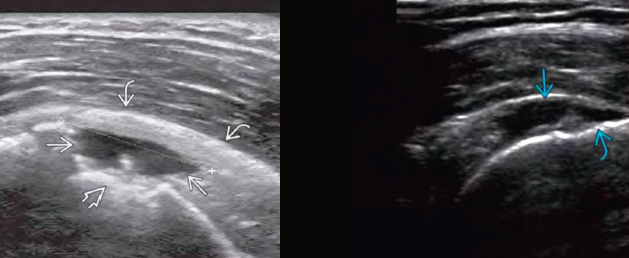

Q

Desgarro de manguito rotador

Rotura y pinzamiento del tendón

Sensibilidad y especificidad del US

90%